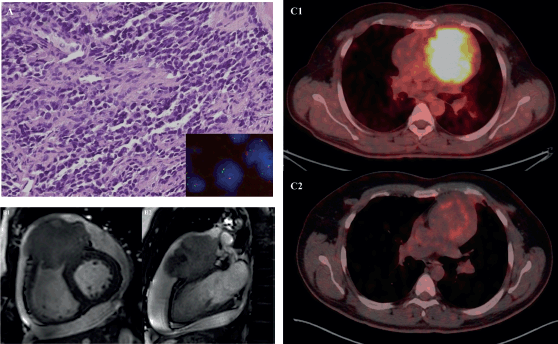

Figure 3. 31-year-old male with desmoplastic small round cell tumour arising from right ventricular outflow tract – (a): Histological photomicrograph showing a malignant round cell tumour with undifferentiated tumour cells with high NC ratio and scanty cytoplasm. (H&E 200×); FISH performed using fusion probes for Ewsr1-WT1 gene showing fused signals indicating EWSR1-WT1 fusion (Inset); (b): Cardiac MRI – short axis view (B1) and 2 chamber view (B2) showing expansile proliferative mass lesion involving the right ventricular outflow tract; (c): FDG PET-CT before (C1) and after (C2) 6 cycles of VAC chemotherapy.